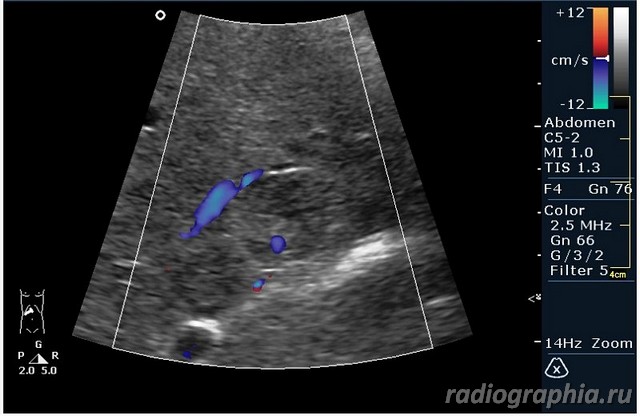

УЗИ печени. Женщина 37 лет. Жалобы на боли в эпигастрии; в печени обнаружено такое образование...

так и хочется назвать это метастазами но уж очень они красивые и доброжелательние по структуре (изоехогенные по отношению к структуре печени) и они больше компресирують чем проростают, склонен к ответу о доброкачественной гиперплазии. так что же на КТ?

гемангиома,рядом питающий сосуд

Мне тоже нравится версия, что это - гемангиома.Нелли писал(а):гемангиома,рядом питающий сосуд